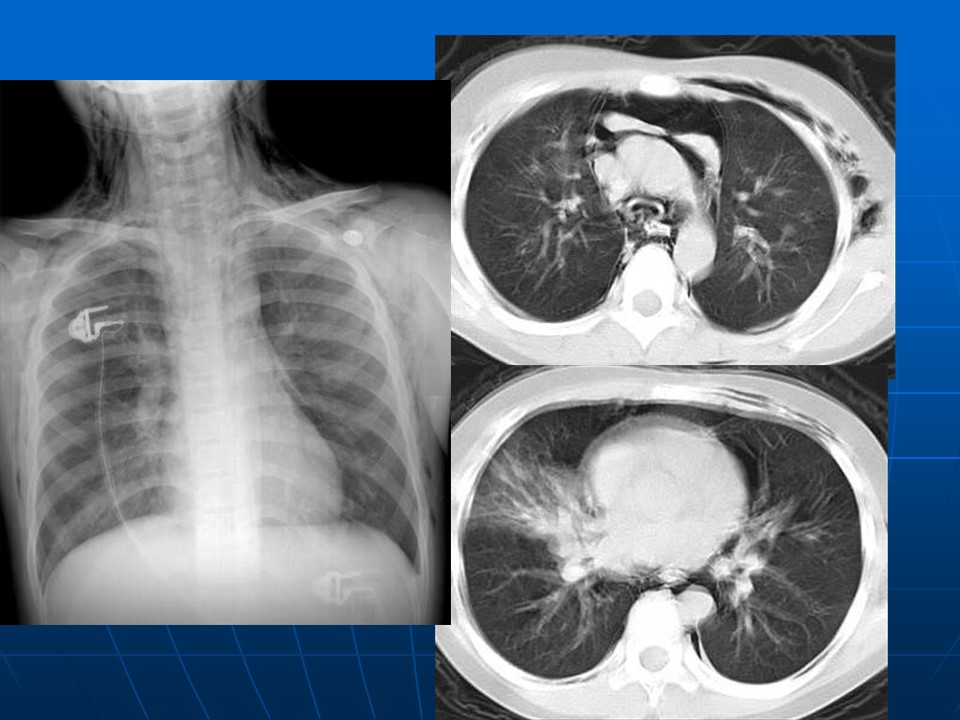

如何在影像上判断新冠病毒肺部感染是否好转